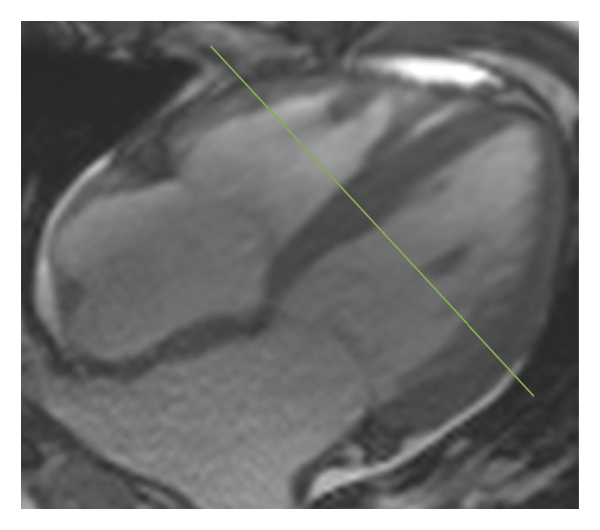

2.3. 이미징 분석모든 이미지 분석은 시중에서 판매되는 소프트웨어(cvi42, Circle Cardiovasic Imaging, Inc. Calgary, Canada)를 사용하여 수행되었습니다. 심장 기능을 측정하기 위해 심장내막 및 심외막 추적을 확장기 말기 및 수축기 말기의 직렬 단축 슬라이스에서 수동으로 수행했습니다. LV/RV 확장기말 용량(EDV), 수축기말 용량(ESV) 및 LV/RV 박출률을 포함한 전체 LV/RV 수축기 기능이 계산되었습니다. LV 및 RV 심근 스트레인 분석은 장축 4챔버 및 단축 슬라이스를 조직 추적 모듈에 로드하여 수행되었습니다(그림 1 (a) 및 1 (b)). RVT는 중실의 3회 측정하였고, 평균 두께를 계산하였다(도 1 (c) 및 1 (d)). GRPS(글로벌 라디칼 피크 변형), GLPS(글로벌 세로 피크 변형) 및 GCPS(글로벌 원주 피크 얼룩)를 포함하여 전역 특징 추적 매개변수가 자동으로 획득되었습니다. 최고 수축기 변형률(PSSR, 이완기부터 다음 수축기까지의 모든 단계에 대한 절대값의 최대 변형률)과 최고 확장기 변형률(PDSR, 수축기부터 다음 수축기까지 모든 단계에 대한 절대값의 최대 변형률)은 다음과 같습니다. 또한 분석했다. 양수 기호와 음수 기호는 서로 다른 동작 방향을 나타냅니다. 앞서 기술한 바와 같이[ 16 ], 정상적인 RVT 값은 7mm 이하로 정의되었다. 기준에 따라 CA 및 HCM 환자를 RV 비대(RVT >7 mm) 또는 RV 비대(RVT ≥7 mm) 환자에 따라 하위 그룹으로 나누었습니다.

(씨) -